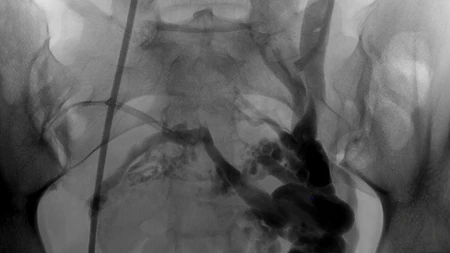

Einspruch zum Zweitmeinungsverfahren bei Aortenaneurysmen-Eingriffen